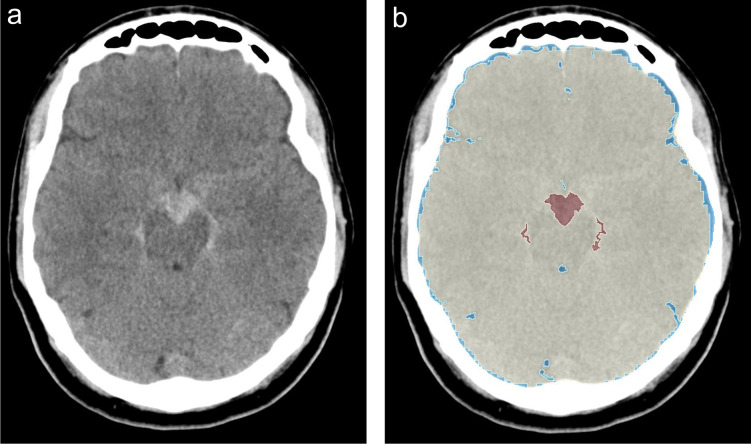

Introduction: Perimesencephalic subarachnoid hemorrhage (pmSAH) is a rare, typically benign subtype of non-aneurysmal subarachnoid hemorrhage (SAH). While the majority of patients demonstrate a positive recovery trajectory, a subset of patients experiences complications, including vasospasm, hydrocephalus, or delayed cerebral ischemia (DCI). Reliable imaging markers for risk stratification are lacking. This study evaluates whether volumetric CT-based biomarkers-validated in aneurysmal SAH (aSAH)-are also predictive for pmSAH.

Methods: In this retrospective single-center study, 72 patients with confirmed pmSAH between 2011 and 2024 were analyzed. The automated volumetric segmentation was performed using 3D Slicer and TotalSegmentator to quantify intracranial volume (ICV), brain volume (BV), cerebrospinal fluid (CSF), and selective sulcal volume (SSV). The associations between volumetric parameters and clinical presentation, complications, and functional outcome (Glasgow Outcome Scale, GOS) were assessed using non-parametric statistics and Spearman correlation.

Results: The median intracranial volume was 1352.7 mL, brain volume 1247.3 mL, cerebrospinal fluid volume 95.9 mL, and selective sulcal volume 19.4 mL. Vomiting at presentation was associated with higher CSF and SSV values (p = 0.04 and p = 0.005, respectively), but no significant volumetric differences were found regarding other symptoms or complications (vasospasm, hydrocephalus, DCI). GOS scores were uniformly high (median = 5), and none of the volumetric markers significantly correlated with outcome or complication rate (all p > 0.05).

Conclusion: In contrast to aSAH, volumetric CT biomarkers such as ICV, BV, CSF, and SSV do not offer predictive value in patients with pmSAH. Risk stratification should continue to rely on initial hemorrhage pattern and volume, clinical monitoring, and individualized assessment rather than other volumetric parameters.